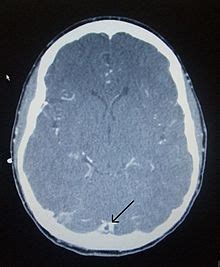

(a) ct scan of head with contrast (1 mm axial) showing left transverse sinus thrombosis. Recommendations on the evaluation and management of cerebral venous thrombosis during pregnancy and in the pediatric population are provided. Do, m.d.department of neurosurgery & interventional neuroradiology, stanford. It's most common clinical manifestations are headache, seizures. Another had involvement of the straight sinus, vein of galen, and internal cerebral veins;

Efns guideline on the treatment of cerebral venous and sinus thrombosis. (a) ct scan of head with contrast (1 mm axial) showing left transverse sinus thrombosis. An unusual diagnosis and management of cerebral venous thrombosis: Demographics of affected patients reflects underlying predisposing factors, which are identified in the majority of cases (87.5%) with many patients having. Another had involvement of the straight sinus, vein of galen, and internal cerebral veins; Common subtypes include transverse sinus thrombosis and superior sagittal sinus. Silvis, sini hiltunen, et al. Cerebral venous thrombosis (cvt) or cerebral venous sinus thrombosis (cvst):